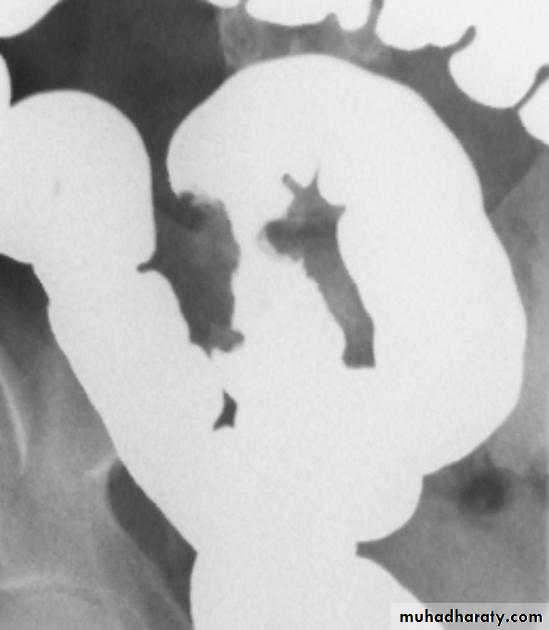

• Cobblestoning-irregular, blanket-like appearance to bowel wall caused by criss-crossing longitudinal and transverse ulcers separated by areas of edema

• String-sign-marked narrowing of terminal ileum (usually) from a combination of edema, spasm and (sometimes, but not always) fibrosis; frequently associated with proximal dilatation